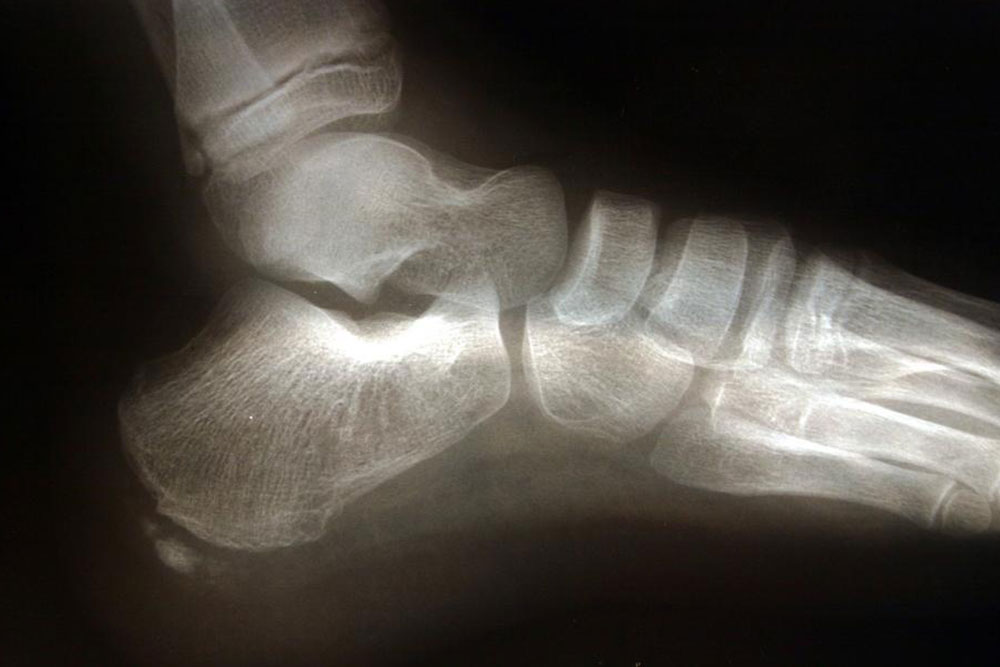

Commonly affecting athletes who frequent activities include running and jumping, heel spur is caused due to calcium deposits on the underside of the heel bone. The symptoms include inflammation of tissues and tendons near the spur, pain while walking or jogging, formation of calluses, swelling or redness of the affected part of the heel.